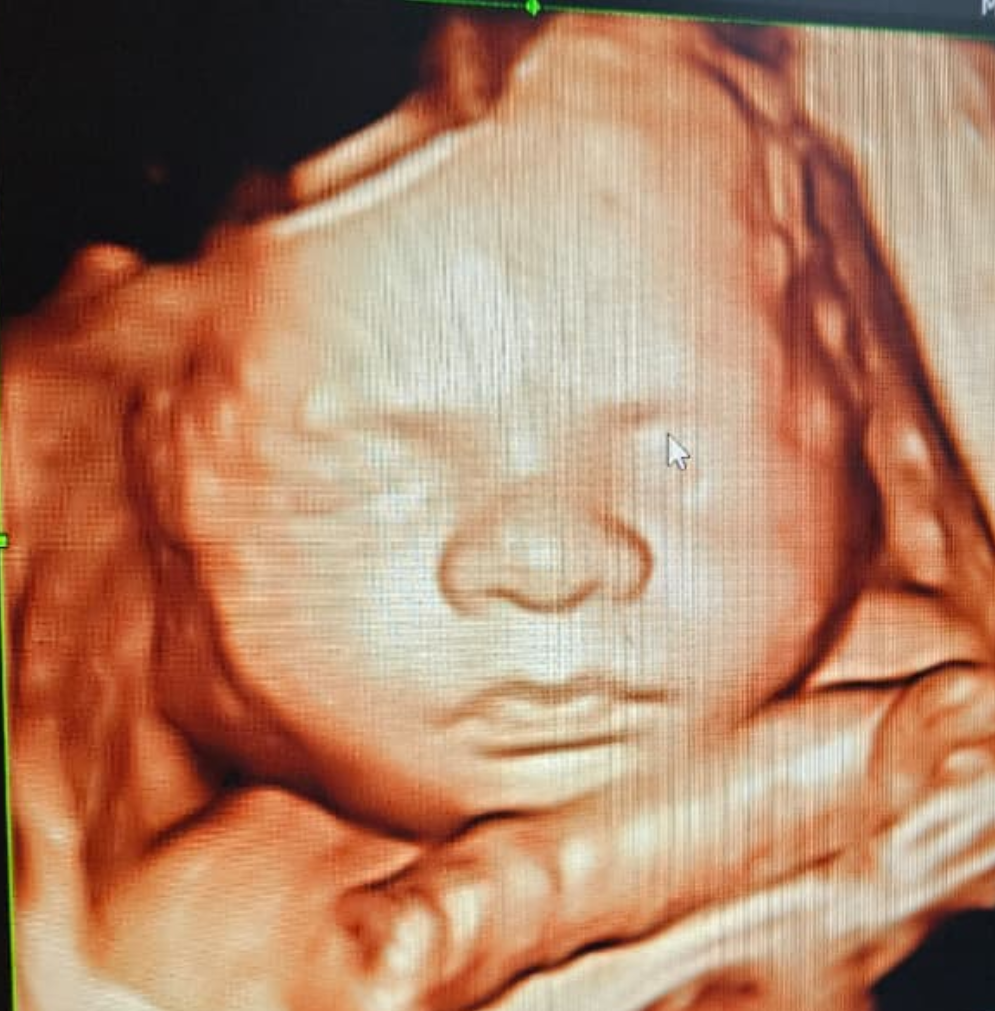

A glimpse of little smiles and joy

Explore our journey of advanced treatments, cutting-edge technology, and compassionate care. Our gallery showcases real procedures, patient stories, and the environment where healing begins.

3D Imaging

3D Photo